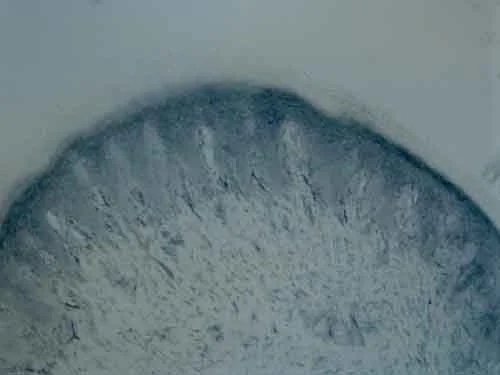

Immunohistochemistry (PFA perfusion fixed frozen sections) - Anti-Tyrosine Hydroxylase antibody - Neuronal Marker (AB137721)

Immunohistochemical analysis of paraformaldehyde-fixed frozen sections of Rat hindlimb pad skin tissue labelling Tyrosine Hydroxylase with ab137721 at 1/100 dilution.